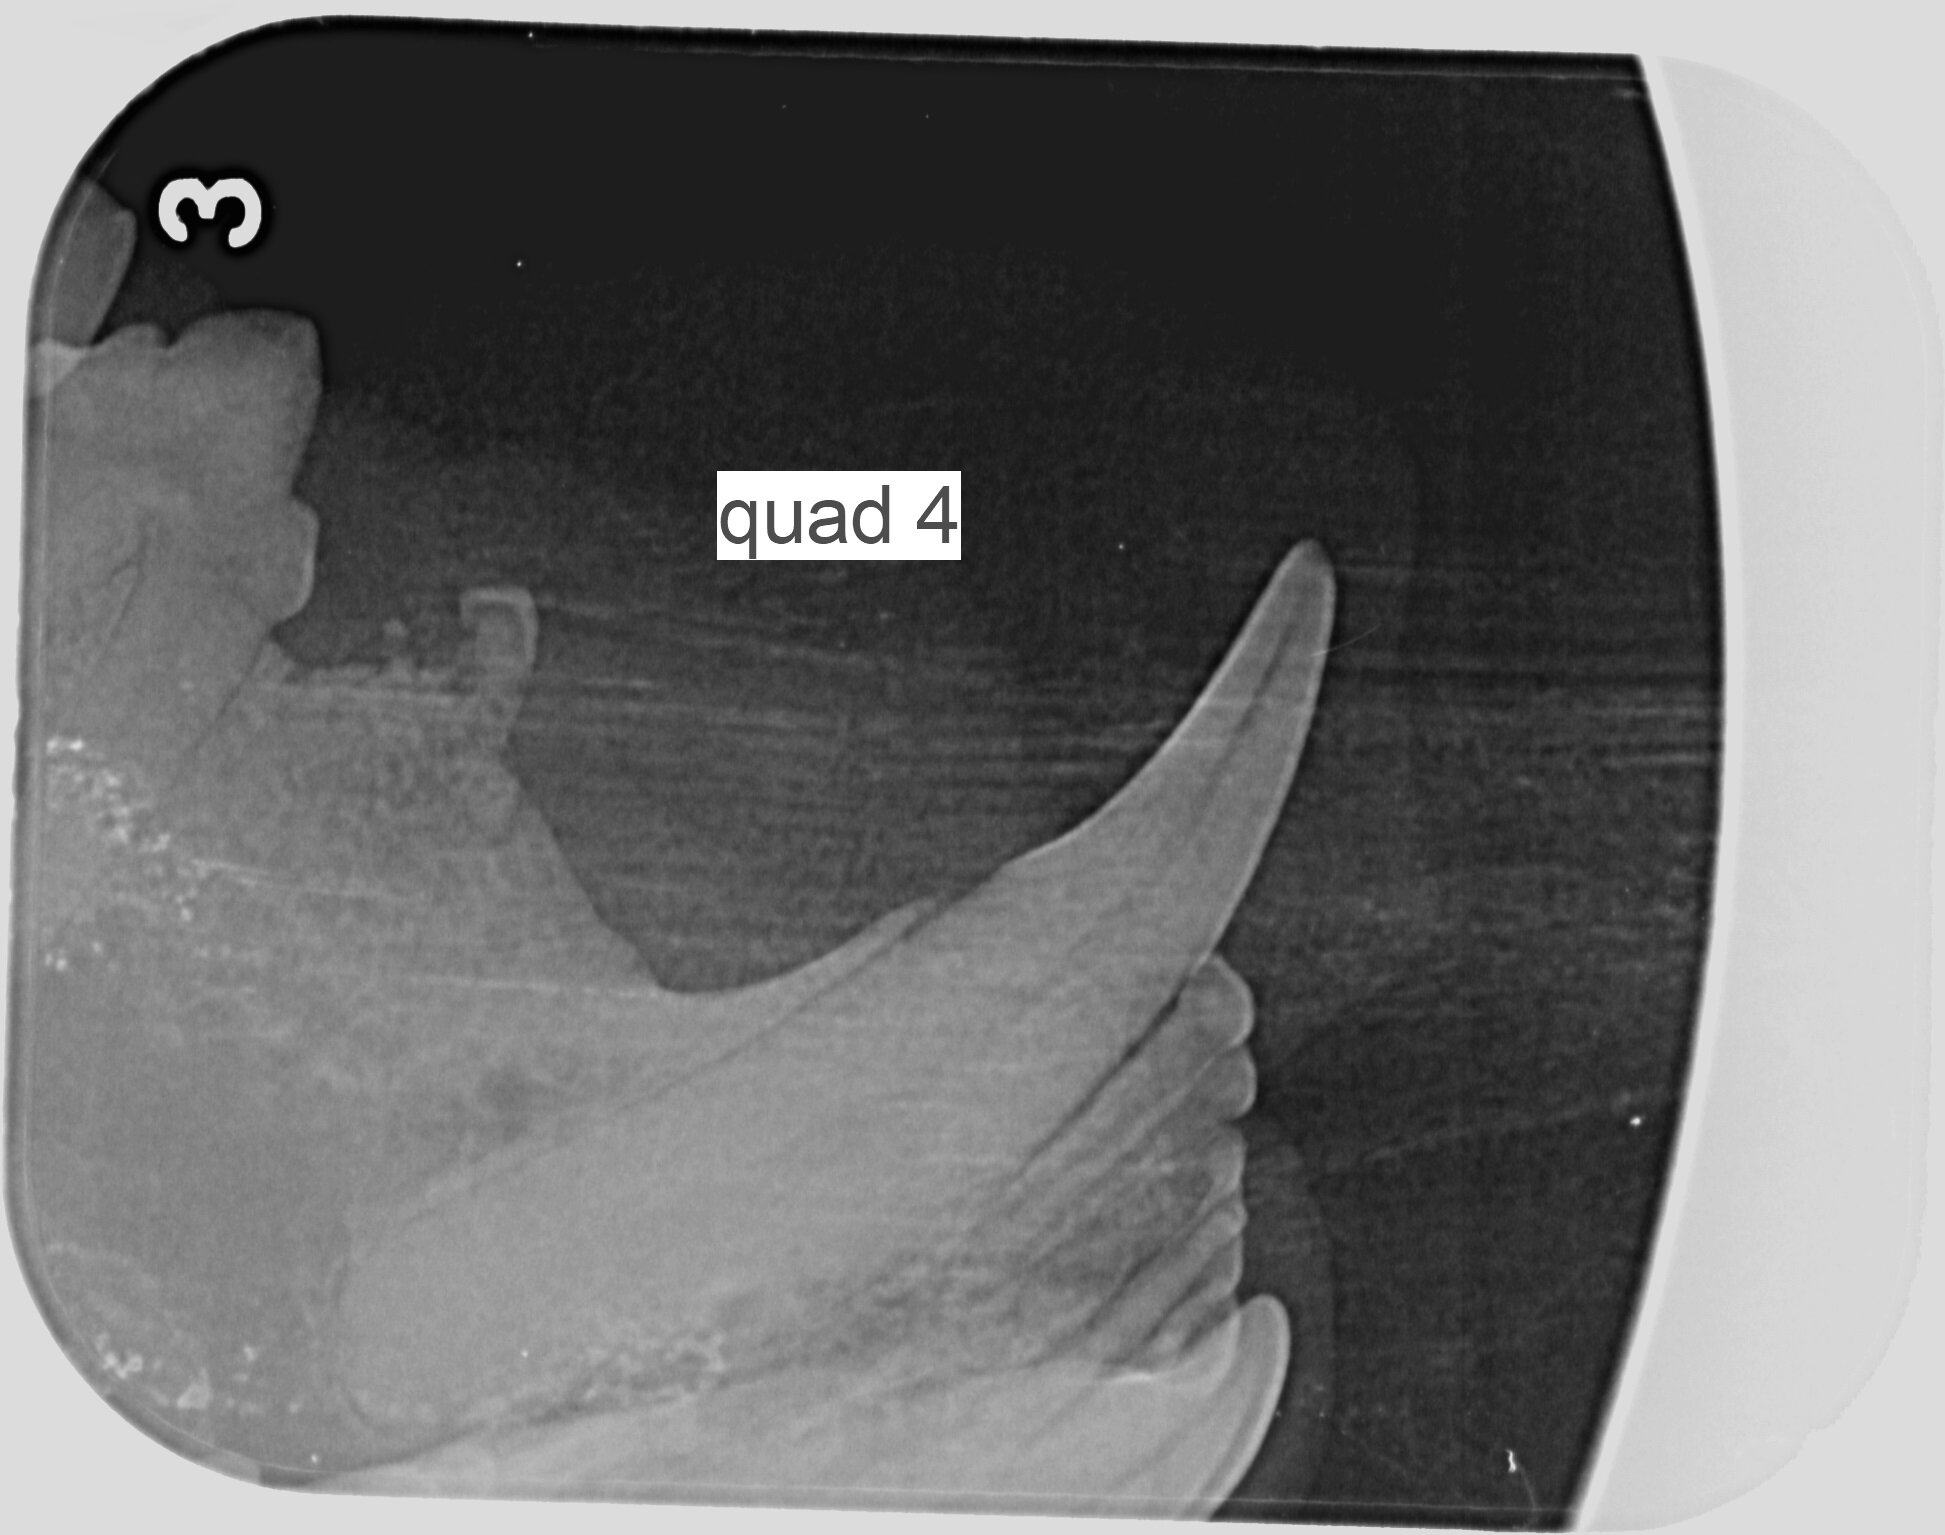

Our Vet, Emily performed the procedure. The x-rays showed that Sox had resorptive lesions on some of the teeth. A resorptive lesion (RL), also known as a neck lesion, is a tooth defect caused by the action of cells called odontoclasts. Tooth structure is destroyed and they can affect both the roots and the crown.

Resorptive lesions are not always visible to the naked eye due to them starting below the gum line. The appearance on the tooth may be hidden by an overgrowth of gum tissue (gingiva). The tooth may also have a pink spot, or part of the tooth may be missing. Often, missing teeth in cats were originally teeth with resorptive lesions. Many of these lesions are only identified using dental radiographs (x-rays), hence the reason that all of our patients undergoing dental treatment have x-rays taken. Currently, the only treatment option for teeth with these lesions is extraction.